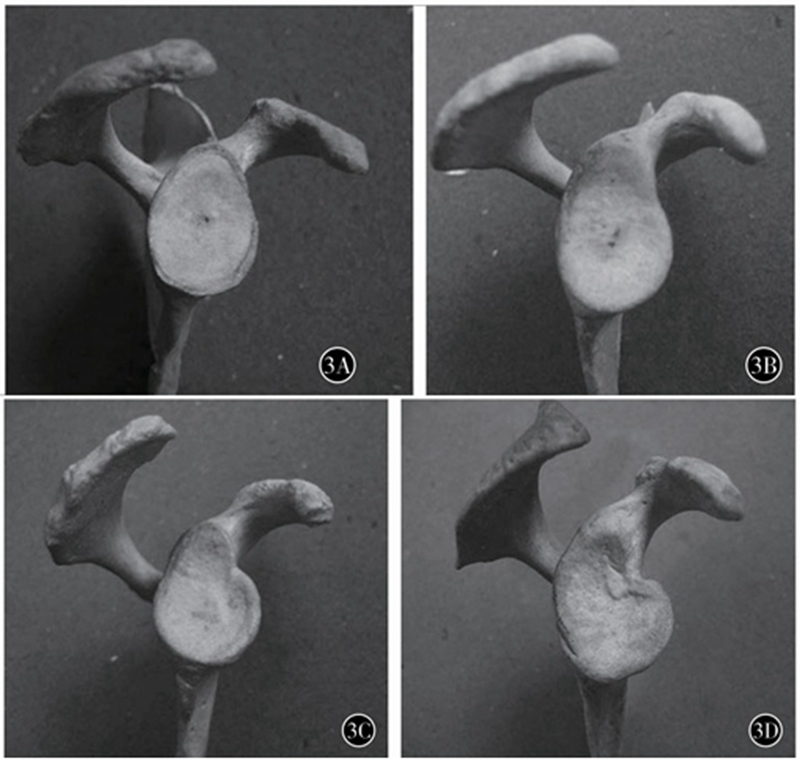

肩胛骨位于胸廓上方两侧偏后,紧贴胸后壁,与其构成类似关节的结构,称之为肩胛胸壁关节。肩关节活动时,肩胛骨沿胸壁活动,配合盂肱关节,完成肩关节上举,是肩关节的重要组成,并通过盂肱关节和肩锁关节将上肢连接于躯干上。 肩胛盂作为盂肱关节的组成部分,深度较浅,形态不规则,近似梨形;下半部分较上半部分大,比例约为1:0.8±0.1。众多研究测量了肩胛盂表面解剖学参数,其中肩胛盂上下径为肩胛盂最高点至最低的距离(图2) ; 其均值男女分别为33.6~37.5mm和29.4~33.8mm。肩胛盂前后径为位于与肩胛盂上下轴垂直平面的肩胛盂前后的最大距离;其均值分别为24.9~28.6mm和21.3~23.7mm。肩胛盂上下径、前后径存在显著的性别差异,男性肩胛盂较女性大10%左右。肩胛盂形态在性别上也有不同,男性肩胛盂下部较圆, 而女性为椭圆。Andrea等依据肩胛盂前缘切迹的形态将肩胛盂的形状分为 4 型(图3) : 0型(无切迹) 、Ⅰ型( 弧线型) 、Ⅱ型(切迹型) 、Ⅲ型(圆齿型) 。男女均以Ⅰ型(弧线型) 所占比例最高。肩胛盂前缘切迹在女性中出现的比例为80.4%;而男性中这一比例为 57.6% 。36.7%的女性切迹出现在顶部;而男性只有28.9%,两者差异有统计学意义。

图3 肩胛盂分型示意图A 0型(无切迹) BⅠ型(弧线型) C Ⅱ型(切迹型) D Ⅲ型(圆齿型)